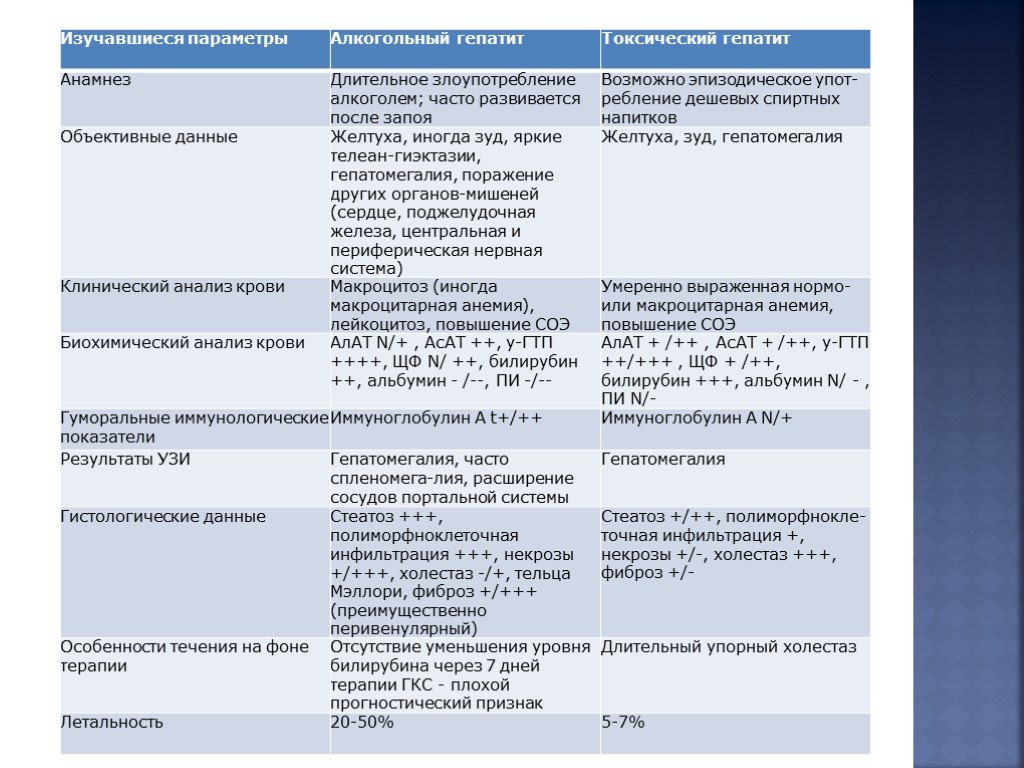

Дифференциальная диагностика заболеваний плевры